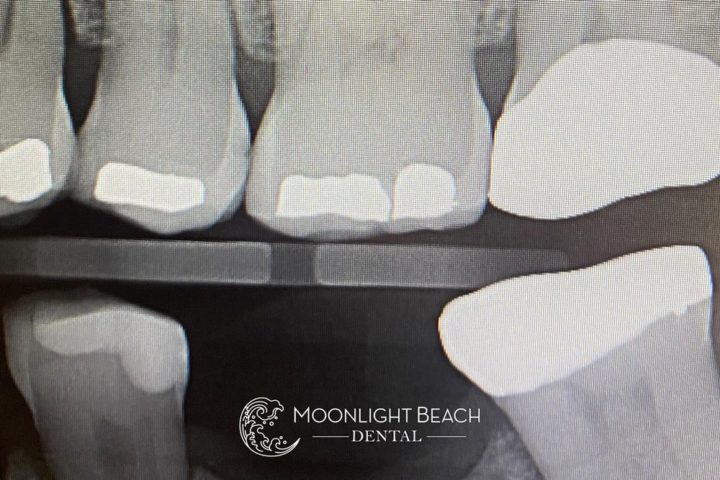

10/10 dentists would say these failing mercury fillings all need crowns. See the fractures?

With our technology, I am able to safely remove the amalgam and explore the depth of the fractures.

I fiber-reinforce them and bond the enamel to the cracks to prevent the need for crowns and (hopefully) future root canals.

For the teeth in all of the photos above, we did 4 very large fillings. The patient left extremely happy with the result, which you can see an example of in the photo below.